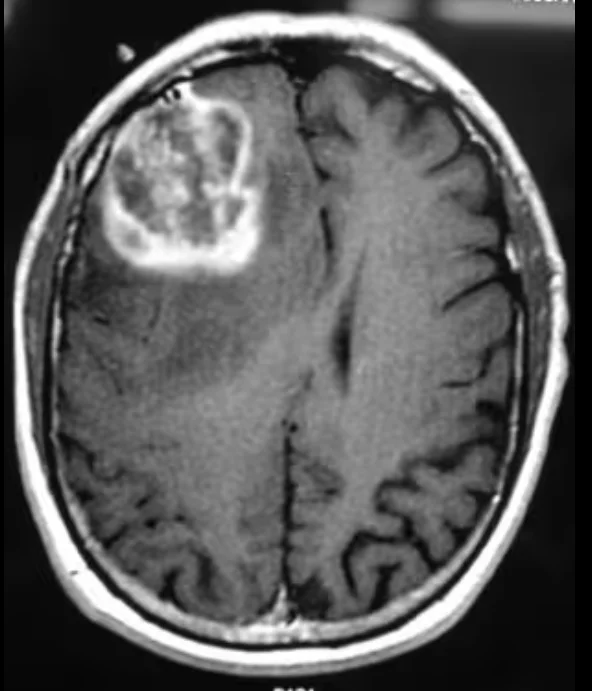

The diagnostic journey usually begins with a contrast-enhanced MRI scan, which provides detailed images of the brain and helps doctors assess the tumor’s size, location, and behavior.

- Glioblastoma often appears as an irregular, aggressive-looking mass. It typically shows uneven contrast enhancement, significant surrounding brain swelling (edema), and dark central areas that represent dead or necrotic tissue. These features suggest rapid growth and infiltration into nearby brain tissue.

- Lower-grade gliomas, on the other hand, usually look more uniform and well-defined. They tend to grow more slowly, cause less swelling, and often lack areas of tissue death. Some may not enhance strongly with contrast at all.

While MRI provides strong clues, imaging alone cannot confirm the exact tumor type or grade.